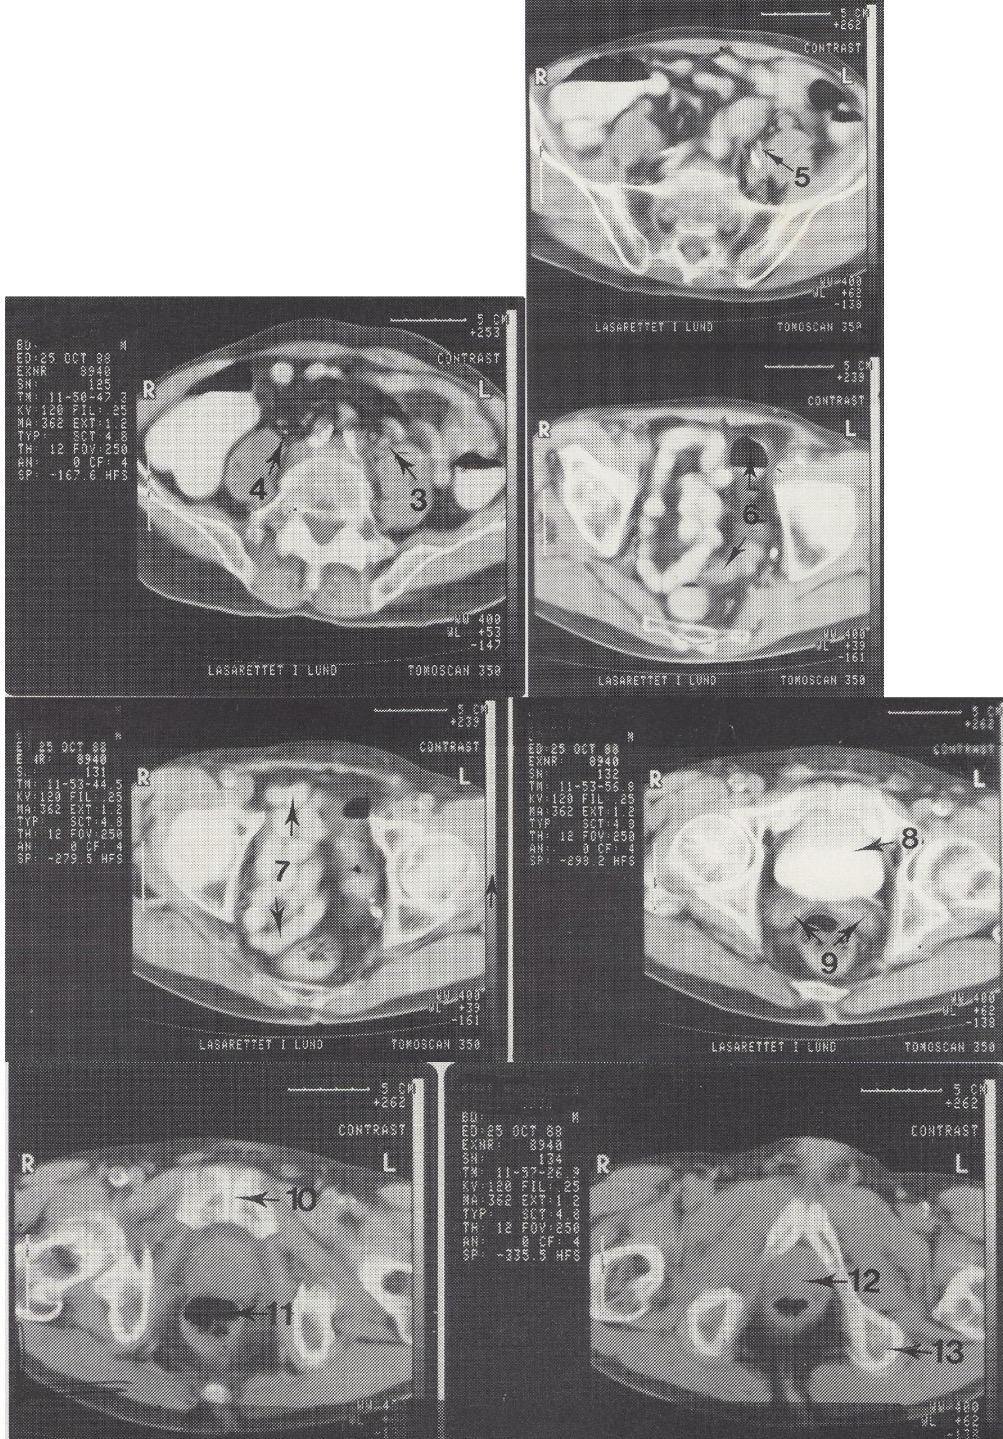

1

Aorta abdominalis (kalcifikuota pilvinė aorta)

2

M. psoas major (didysis juosmens raumuo)

3

Ureter sinister (kairysis šlapimtakis, šiek tiek praplėstas)

4

Ureter dexter (dešinysis šlapimtakis)

5

A. iliaca interna sin. (kairioji vidinė klubo arterija)

6

Colon sigmoideum (riestinė žarna)

7

Ileum kilpos dubenyje (tuščiosios žarnos kilpos)

8

Vesica urinaria (šlapimo pūslė, užpildyta kontrastu)

9

Vesiculae seminales (sėklinės pūslelės)

10

Symphysis pubica (gaktinė sąvarža)

11

Rectum (tiesioji žarna)

12

Prostata (priešinė liauka)

13

Tuber ossis ischii sin. (kairysis sėdimasis gumburas)

Metodika

KT pjūviai nuo juosmens slankstelių iki gaktinės sąvaržos apačios. Suleistas intraveninis kontrastas (išryškina šlapimo takus) ir išgertas kontrastas (išryškina žarnyną).

Radiniai

Gausūs apkalkėjimai (kalcifikatai) aplink pilvinę aortą ir vidines klubo arterijas. Kairysis šlapimtakis matomas priešais m. psoas major, jis šiek tiek išsiplėtęs.